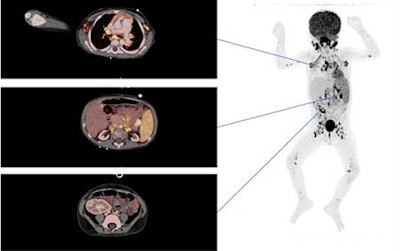

Above: An FDG-PET/CT scan of a 3-year-old kidney and liver recipient with fever shows increased FDG uptake in enlarged and normal-sized lymph nodes above and below diaphragm, including the extremities. Below: The patient was in complete remission after three weeks of treatment. The area with increased FDG retention in the right fossa corresponds to urine excretion in the well-functioning graft. Images courtesy of EJNMMI.FDG-PET/CT achieved sensitivity of 97%, specificity of 84%, positive predictive value of 87%, and negative predictive value of 96%.